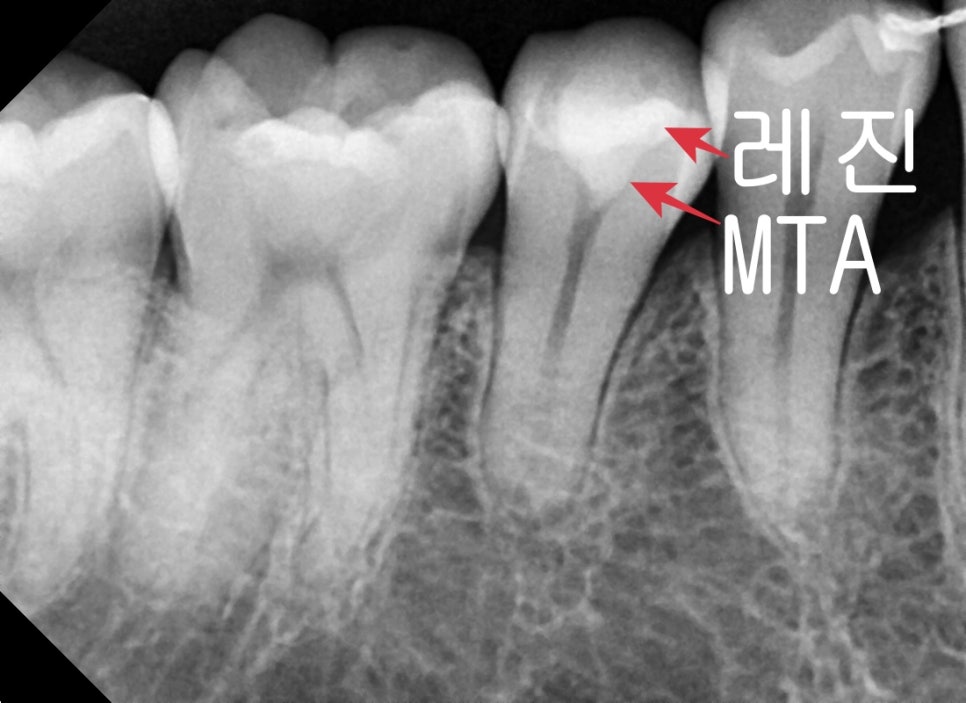

치료 후 사진입니다.

노출된 신경관 입구에 MTA 재료를 쌓아 올린 후 경화된 후

상부에 튼튼하고 심미적인 레진 치료 후 마무리를 했습니다.

신경이 살아있고 노출 범위가 넓지 않기 때문에 MTA 재료의 아주 좋은 케이스입니다.

무조건 신경치료를 하면 안 된다 안 좋다 보다 꼭 필요할 때는 해야 하지만

적응증을 잘 골라내어 올바른 재료를 적용한다면 조금 더 보존적인 치료를 할 수 있게 됩니다.